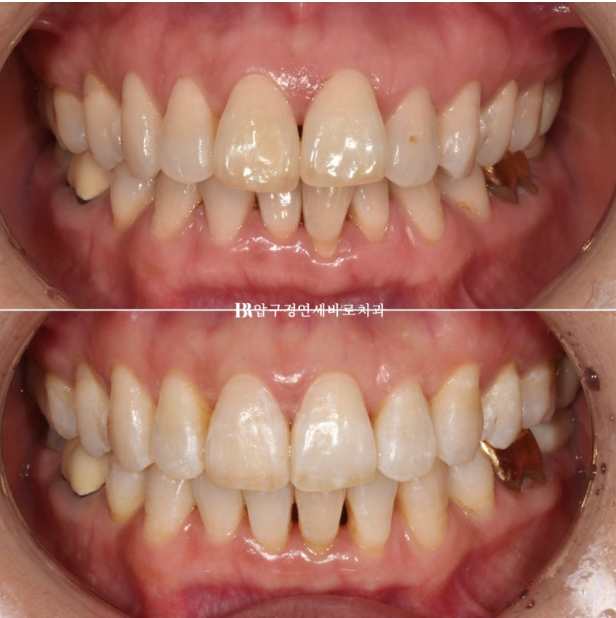

뻗친 앞니 각도가 개선이 되고 나비치아 토끼이가 배열이 되었습니다.

이 정도도 충분히 좋지만 100점 목표를 위해 추가장치 제작을 합니다.

추가장치를 2월부터 5월까지 3달간 10일씩 꼈고 마무리 했습니다.

24.05

위 앞니 블랙트라이앵글은 치간삭제를 통해 줄었으나 삐뚤했던 아래 앞니가 가지런해지면서 블랙트라이앵글이 생겼습니다.

아래도 마찬가지로 치간삭제를 통해 블랙트라이앵글 사이즈를 줄였지만 치간삭제는 치아에 무리가지 않는 선에서 하는 것이 좋습니다.

걱정하시는 교합도 좋습니다.